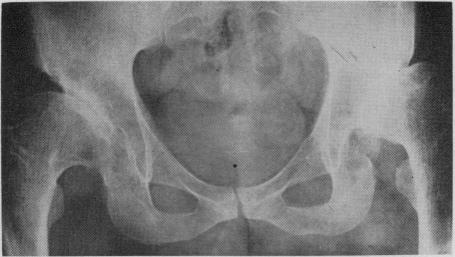

Etiology, pathogenesis and possible prevention of congenital dislocation of the hip.

Can Med Assoc J. 1968 May 18;98(20):933-45.